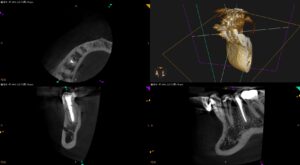

軟らかいものも噛めなかった右下小臼歯〜#29 Re-RCT 7yr recall

紹介患者さんのリコール。 治療したのは2016年だったので、実に… 7年ぶりである。 あの後、私は頭をやって倒れて一命を取り留めた。 患者さんも病気をされて入院したという。 変わらず、健康に日々を生きることがどれほどあり … 続きを読む 軟らかいものも噛めなかった右下小臼歯〜#29 Re-RCT 7yr recall